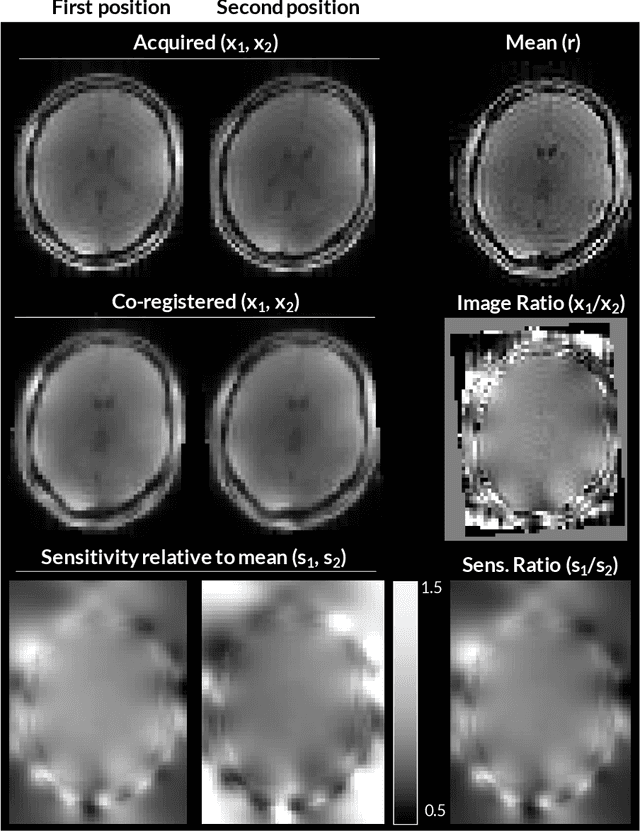

Abstract:Purpose: Inter-scan motion is a substantial source of error in $R_1$ estimation, and can be expected to increase at 7T where $B_1$ fields are more inhomogeneous. The established correction scheme does not translate to 7T since it requires a body coil reference. Here we introduce two alternatives that outperform the established method. Since they compute relative sensitivities they do not require body coil images. Theory: The proposed methods use coil-combined magnitude images to obtain the relative coil sensitivities. The first method efficiently computes the relative sensitivities via a simple ratio; the second by fitting a more sophisticated generative model. Methods: $R_1$ maps were computed using the variable flip angle (VFA) approach. Multiple datasets were acquired at 3T and 7T, with and without motion between the acquisition of the VFA volumes. $R_1$ maps were constructed without correction, with the proposed corrections, and (at 3T) with the previously established correction scheme. Results: At 3T, the proposed methods outperform the baseline method. Inter-scan motion artefacts were also reduced at 7T. However, reproducibility only converged on that of the no motion condition if position-specific transmit field effects were also incorporated. Conclusion: The proposed methods simplify inter-scan motion correction of $R_1$ maps and are applicable at both 3T and 7T, where a body coil is typically not available. The open-source code for all methods is made publicly available.